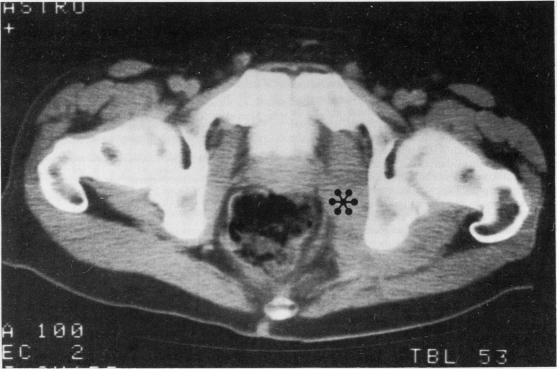

马红球菌,以前称为马棒状杆菌,曾从两名获得性免疫缺陷综合征(艾滋病)患者的血液中反复分离出来。这两名患者在菌血症期间均无肺炎,而在先前报道的所有人类感染马红球菌的病例中均存在肺炎。我们的一名患者有腹泻,该菌从粪便培养物中分离出来;另一名患者盆腔有一个由马红球菌引起的巨大肉芽肿性软组织肿块。两种分离株均对青霉素耐药,其中一株产生β-内酰胺酶。两名患者均接受了万古霉素治疗,但只有一名康复。

https://cdn.ncbi.nlm.nih.gov/pmc/blobs/9d40/1141024/8bb1486d108b/jclinpath00325-0081-a.jpg